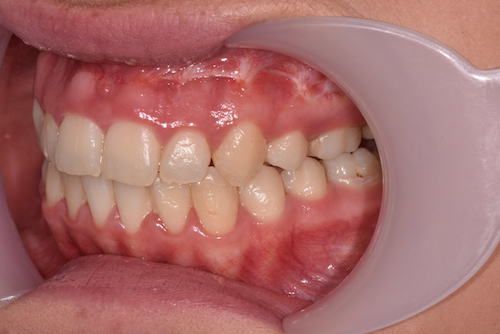

When the bones of the face and jaws are out of balance with each other, orthodontics alone will often not be able to position the teeth in order to create a functional bite. This imbalance between the jaws can result in a combination of problems. These may include:

Your teeth need to be aligned, levelled and moved into the correct position ready for your jaw surgery to take place and remain stable after the surgery. This can often result in your bite becoming worse over the period of orthodontic treatment, but you have to remember that your teeth will be in a better, more stable position after the jaws have been moved into their correct planned position.